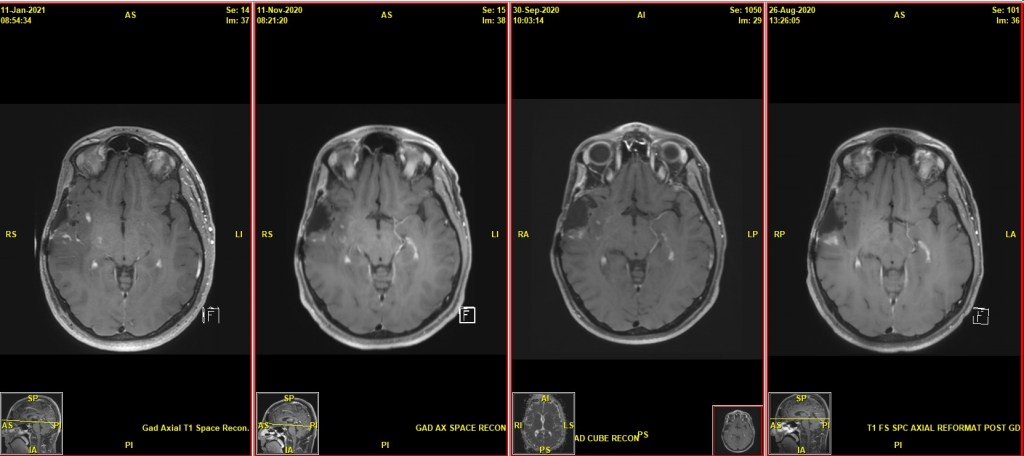

I’m elated, but Dr. R shows me the difference between the August 2020 scan vs. Feb 2021. The tumor appears to be growing, and Dr. R is concerned and thinks we need to start some treatment. Before Monday’s appointment, I sent my case and all my scans to a non-profit organization called Cancer Commons that provides more treatment options based on my individual case. I’ve had a few phone calls with Dr. Deming. All of the physicians who are caring for me are concerned that my tumor is growing again (even before Monday’s scan), and they’ve all suggested I begin some type of treatment as soon as possible.

“I agree with my colleagues in Radiology. There is not a dramatic change between today’s scan and the scan from January 11. The overall trend, however, has been one of potential disease progression.”

-Dr. R Clinical Notes (2/8/21)